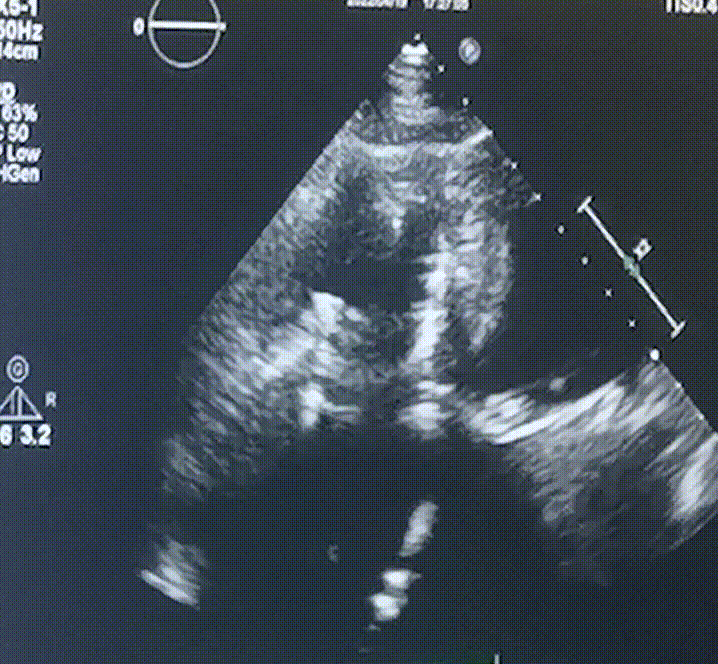

術(shù)前超聲提示:

1.右心、左房明顯增大;

2.二尖瓣人工機(jī)械瓣功能正常,無瓣周漏;

3.三尖瓣環(huán)巨大擴(kuò)張,收縮期瓣葉對(duì)合不攏,收縮期三尖瓣房側(cè)見大量反流信號(hào),反流面積15-20cm²,TRVmax:240cm/s,跨瓣壓差:23 mmHg。

圖1.術(shù)前超聲